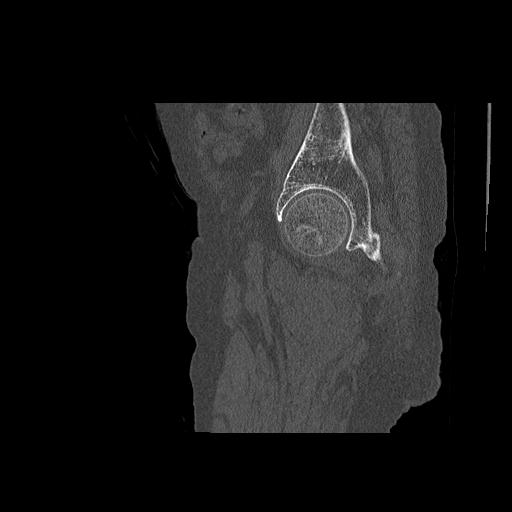

110286 2/17 股関節 2R 74歳女性 右人工骨頭

82084 1/14 1/20 股関節 2R 78歳男性 右人工骨頭

91569 3/25 両股正面とラウエン 70歳女性 人工骨頭+バンクーバー